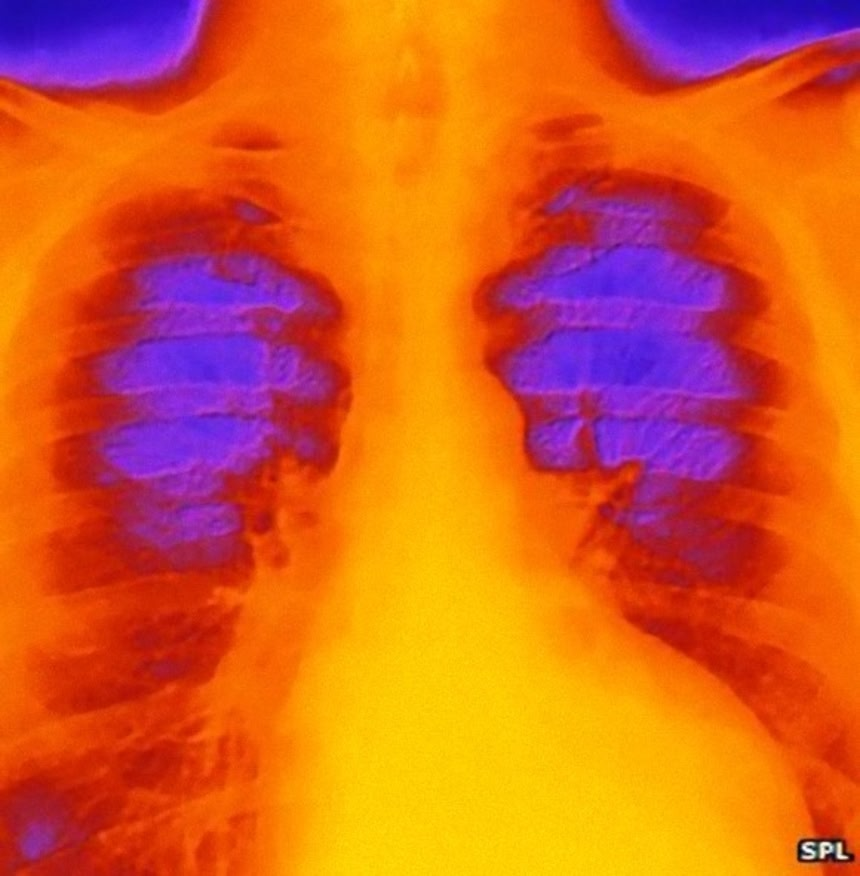

この「傷心シンドローム」は正式には””たこつぼ心筋症(ストレス性心身症)”という。英国心臓基金では「心臓の筋肉が突然衰弱する、または麻痺する一時的な症状。心室の一つ、左心室の形状が変化する」と定義している。突然のストレスによって左心室が膨張し、心臓がたこつぼの様なくびれた形状をとることに由来する。

この画像を大きなサイズで見るこれは強いショックによって引き起こされる。たこつぼ心筋症患者の4分の3が発症前に感情的ないしは身体的ストレスを経験している。死別はもちろんだが、それだけというわけではない。

同僚のいたずらで驚いたり、大勢の前で話すことで受けるストレスによっても罹患したという記録もある。これはアドレナリンなどのホルモンの急激な放出が、心筋の麻痺を引き起こすことが原因と考えられている。したがって血液の供給が阻害されたことで引き起こされる一般的な心臓発作とは別物である。

この画像を大きなサイズで見るたこつぼ心筋症を患う多くの人の冠状動脈はかなり正常な状態にあり、深刻な閉塞が見られない。したがって、やがてストレスが消え去れば、心臓の形状は元の状態へ戻り、自然に回復する。しかし高齢者などの一部の人たちは、これによって致命的な心臓発作が引き起こされてしまう。